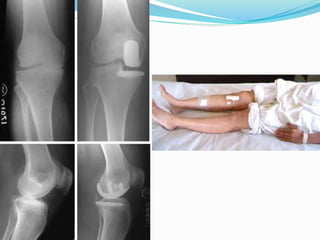

Erect

Postop xrays